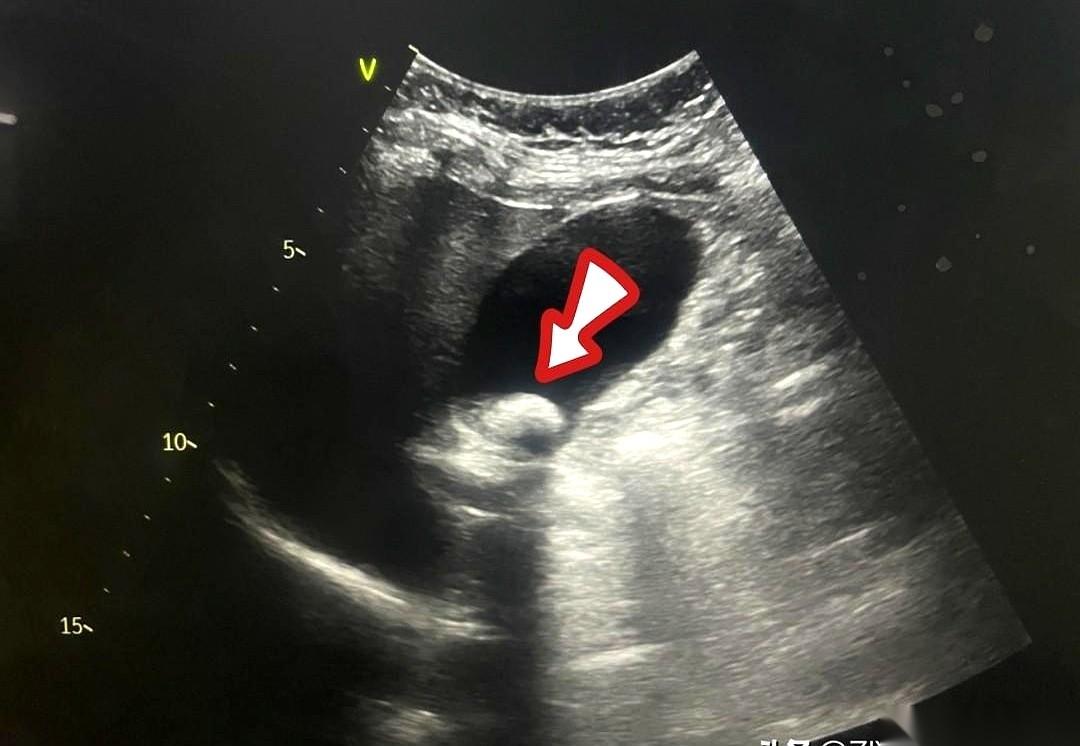

我跟你讲个事儿,绝了。 一个阿姨,肚子疼了20天,跑去做CT,报告白纸黑字写着:胆囊没毛病。 可她就是疼啊!转头又去做了个B超,好家伙,B超上清清楚楚,一堆石头。 同一个胆囊,同一个时间,俩机器,两种命。 这找谁说理去? 后来才知道,石头这玩意儿,也分“三好学生”和“隐形刺客”。 阿姨得的那种,叫胆固醇结石。说白了,就是一肚子“油”结晶了。 这东西密度低,跟胆汁儿差不多。 在普通CT眼里,它俩就是一伙儿的,跟透明的冰块扔进了白开水里一样,根本看不出来。CT报告当然写“没事”。 但B超不一样,它靠的是耳朵,是声波。 石头和液体,在它听来,动静完全不同。一下就给揪出来了。 所以啊,有时候真不是机器骗你。 是你身体里那个“对手”太狡猾。 这事儿给我最大的感触就是,别太迷信一张报告。 尤其是当你的身体还在持续发出警报的时候。 你的疼,你的难受,才是最真实的报告。 机器是死的,人是活的。多问一句,换个法子查,可能就是天壤之别。 千万,千万要信你自己的身体。 它不会骗你。